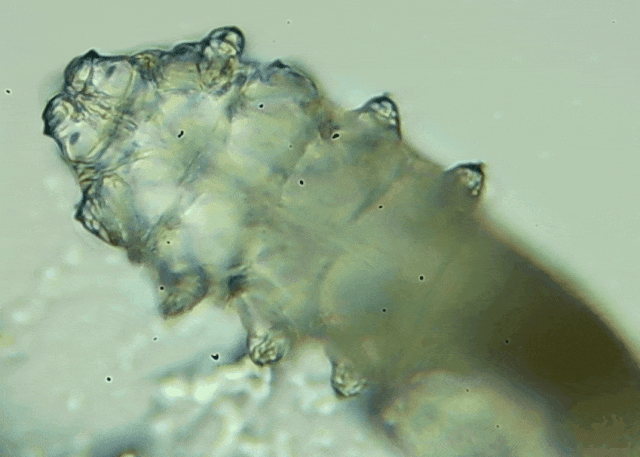

蠕形螨是一類肉眼看不見(jiàn)的寄生螨,常見(jiàn)的有毛囊蠕形螨和皮脂蠕形螨,常駐在人類的毛囊和皮脂腺里,尤其是眼睛的瞼板腺和睫毛根部。數(shù)量少時(shí),蠕形螨能與人體“和平共處”,但一旦你免疫力下降、油脂分泌旺盛或清潔不到位,他們就會(huì)以你難以想象的速度瘋狂繁殖。

睫毛上驚現(xiàn)80只螨蟲(chóng)!【文章導(dǎo)讀】我只是眼睛癢,結(jié)果醫(yī)生說(shuō)我睫毛里有80只蟲(chóng)?這不是恐怖片,而是真實(shí)的病例:武漢一13歲男孩,右眼9根睫毛里檢出39只螨蟲(chóng),左眼9根里檢出47只。 而且這不是極端個(gè)案,廈門眼科中

而且這不是極端個(gè)案,廈門眼科中心干眼門診的臨床數(shù)據(jù)統(tǒng)計(jì),眼睛經(jīng)常紅癢發(fā)炎的人群,多數(shù)都有螨蟲(chóng),約80%以上的瞼緣炎患者螨蟲(chóng)超標(biāo),一根睫毛最多能有幾十只。